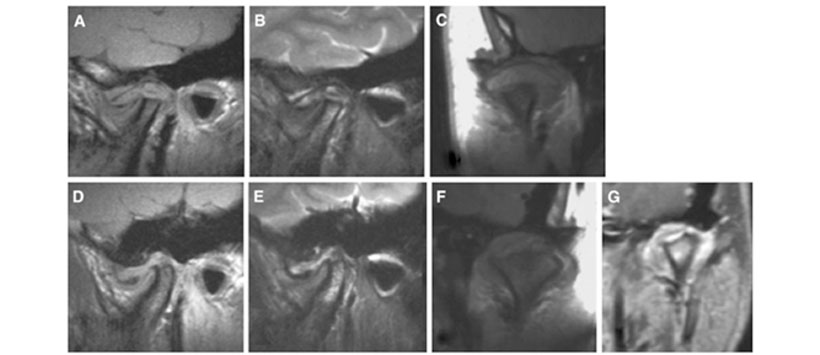

En el primer examen de MRI en la visita inicial (Fig. 1), se observó una ligera erosión del hueso cortical de ambos cóndilos, pero no se observó una deformidad marcada. El disco articular mostró una posición normal en la ATM derecha y desplazamiento anterior en la ATM izquierda. Se observó derrame articular en el espacio articular de la ATM en ambos lados. En las imágenes coronales, se observó proliferación sinovial característica en ambos lados. En el segundo examen de MRI al año después de la visita inicial (Fig. 2), se notó una marcada destrucción del cóndilo y de la fosa articular en la ATM en ambos lados. En las imágenes potenciadas en T2, el proceso condilar que incluye el cóndilo y la fosa articular en ambos lados mostró una alta intensidad de señal, lo que sugiere edema del hueso medular. Tal intensidad de señal alta también se observó en el tejido blando circundante.

En las imágenes coronales, se observó una marcada proliferación sinovial, que mostró una mejora de contraste homogénea en la ATM en ambos lados. En los exámenes de IRM tercero y cuarto, se confirmó que la destrucción ósea había progresado en ambos lados. En particular, en el cuarto examen de MRI a los 2 años después de la visita inicial (Fig. 3), la estructura normal del cóndilo derecho casi había desaparecido.